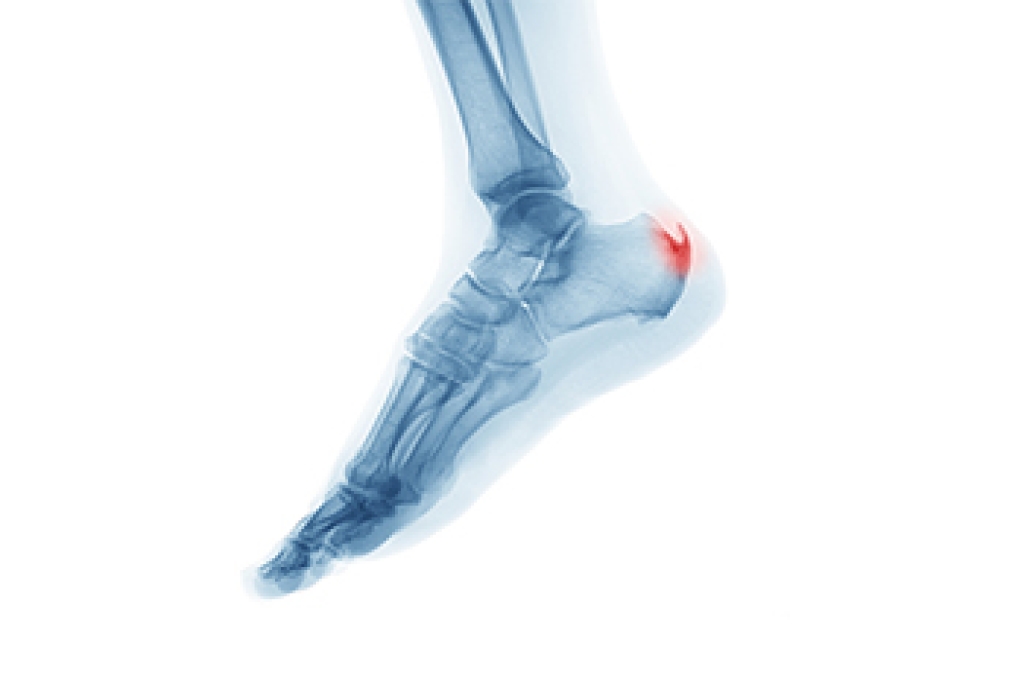

A heel spur is a bony growth that forms on the underside of the heel bone due to prolonged strain on foot muscles and ligaments. It often develops from repeated stress, inflammation, or tension on the plantar fascia. Although heel spurs are commonly associated with plantar fasciitis, they are not the same condition. Plantar fasciitis involves inflammation of soft tissue, while a heel spur is a calcium deposit on the bone. Some heel spurs cause no symptoms, but others can lead to sharp pain in the heel, especially when walking or standing. Discomfort may worsen after rest. A podiatrist can diagnose the condition and recommend appropriate treatment. If you have heel pain, it is suggested that you consult a podiatrist who can provide effective relief and treatment solutions.

Heel spurs are formed by calcium deposits on the back of the foot where the heel is. This can also be caused by small fragments of bone breaking off one section of the foot, attaching onto the back of the foot. Heel spurs can also be bone growth on the back of the foot and may grow in the direction of the arch of the foot.